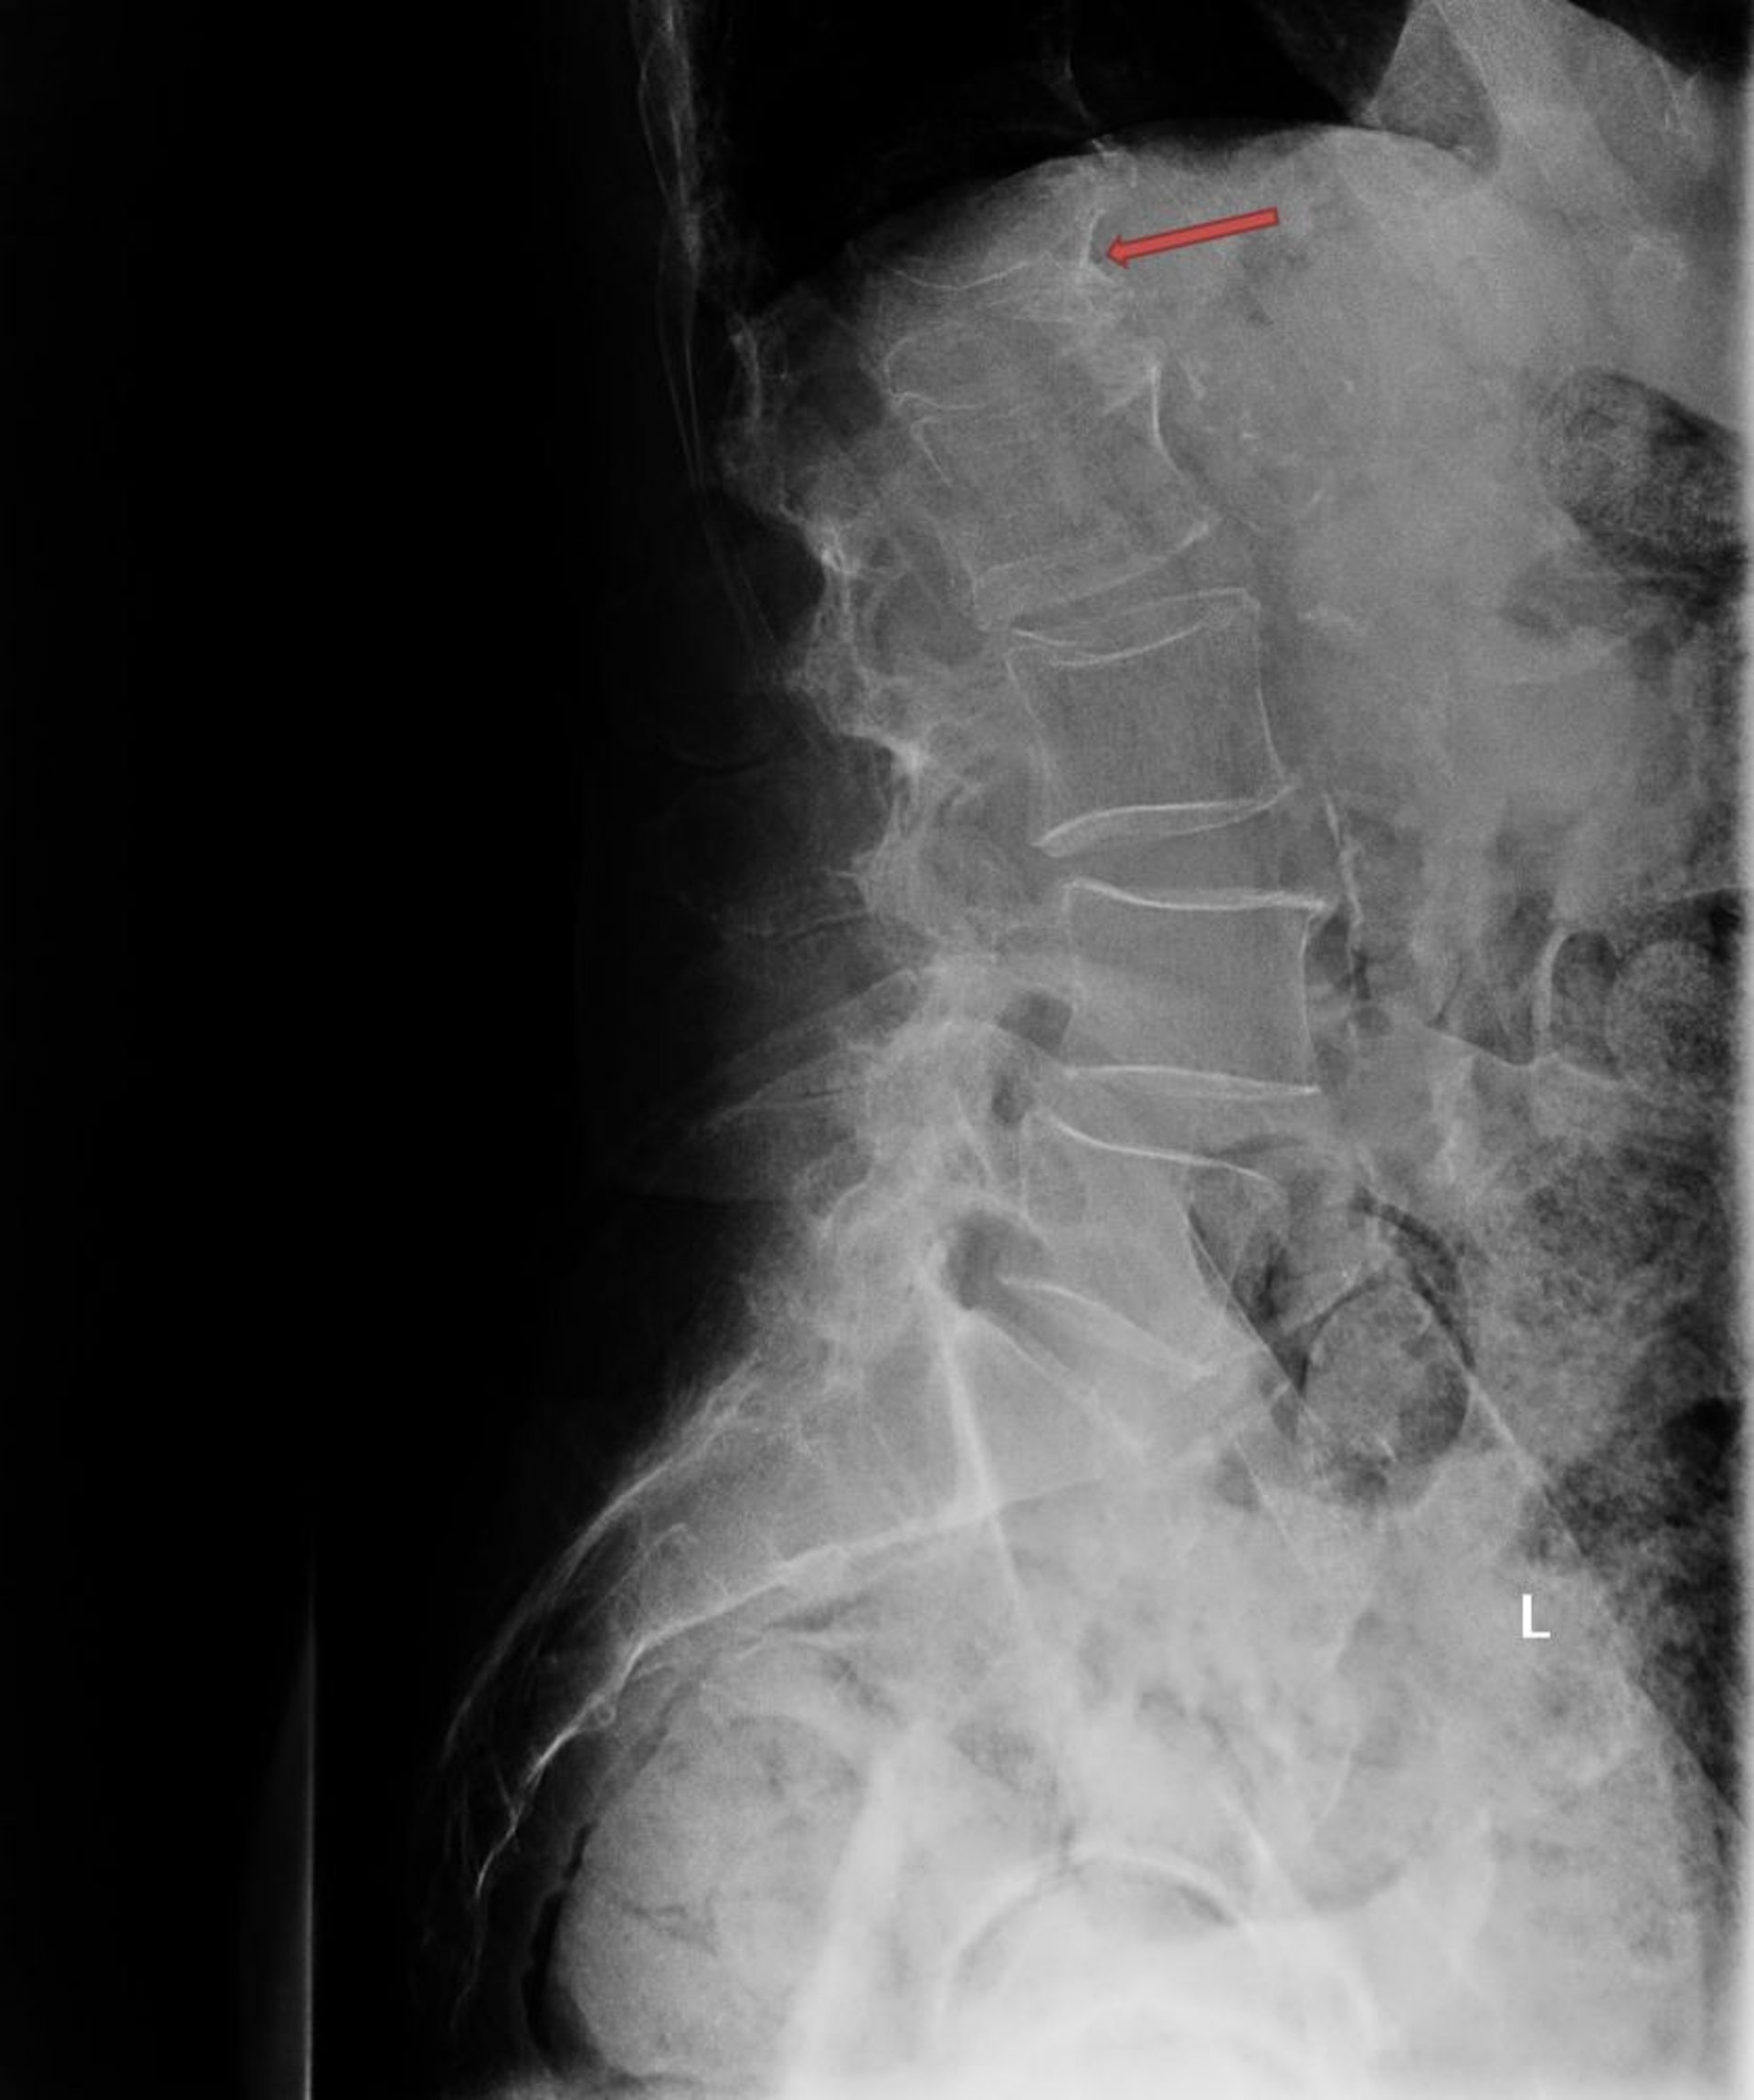

骨粗鬆症性圧迫骨折

このX線写真には,第1腰椎(L1;矢印)の重度の骨粗鬆症性圧迫骨折が写っている。

Photo courtesy of Marcy B.Bolster, MD.